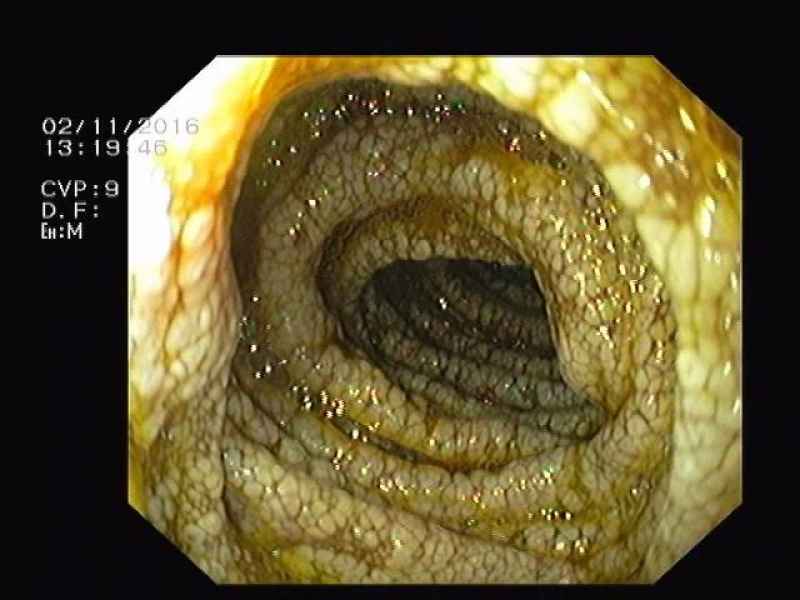

Colocolic intussusception

Fotografia